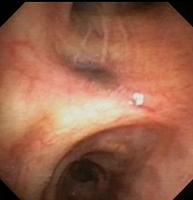

Metastatic melanoma (Narrow band imaging)

Metastatic amelanotic melanoma